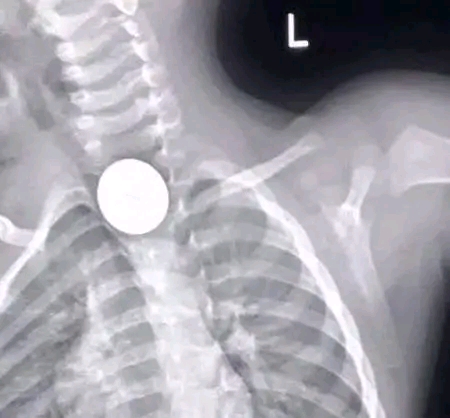

He vomited twice in ER, but was not in Respiratory distress. His Vital Signs were stable, and no abnormalities were detected.X-ray was done and confirmed a Diagnosis of foreign body in Oesophagus.